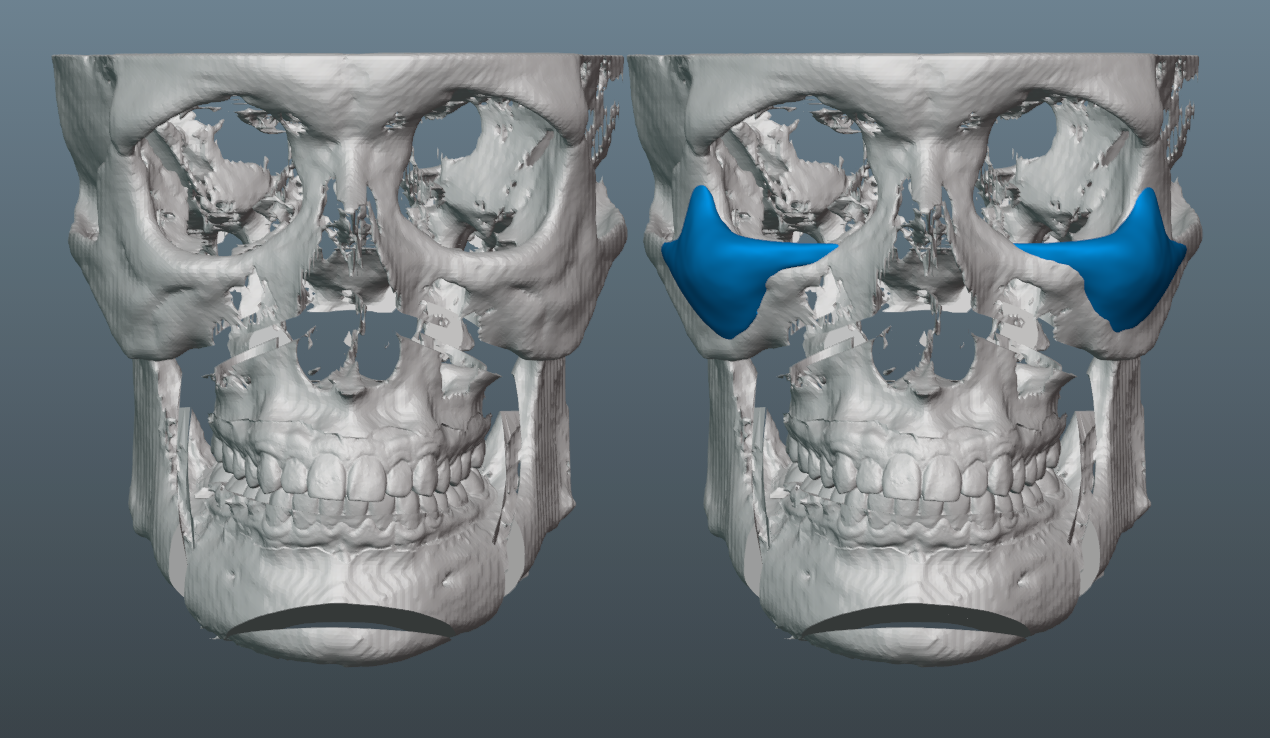

Trimax with around 7mm forward movement and 4mm downgraft.

10.5mm pogonion increase.

Needed a lot of projection on the malar part of the implant, since the patient has a fairly flat midface, which would have been exacerbated by the bimax.

Few key notes and thoughts on the implant design:

-6mm malar projection.

-3mm saddle on the infras.

-Minimal projection on medial part of infra region. This helped keep the taper minimal and avoids too much of the infamous infra implant shelfing/step-off.

-Though we initially tried to do a smaller implant, it became clear that it was necessary to increase its size, so that we could ensure better transitions to the submalar region, zygo arch and lateral orbital rim.